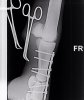

Что касается лечения, то при таких переломах оно также может быть консервативным (полный покой, ортопедическая ковка и/или гипсовая повязка) или хирургическим. При выборе метода лечения врач учитывает тип и место перелома; породу, размер и темперамент лошади, а также ее будущее предназначение. Так, продольные одиночные внутрисуставные трещины или простые переломы в путовой кости имеют гораздо лучший прогноз на восстановление после хирургической фиксации (остеосинтеза). Такая операция проводится под общим наркозом и заключается в фиксации сломанных кусочков костей при помощи специальных пластин и шурупов. При своевременной и удачной операции большинство животных возвращаются к нагрузкам и имеют все шансы работать и не хромать.

Одним из последних ветеринарных достижений при лечении переломов у лошадей, является метод транскортикальной (чрезкостной) фиксации. Смысл такой фиксации заключается в том, что выше места перелома внутри кости временно ставят специальные металлические стержни, а потом всю конечность одевают в легкий и вместе с тем очень прочный полимерный гипс, в котором и закрепляют эти стержни. Таким образом, получается, что конечность лошади выше места перелома как бы подвешивается внутри гипсовой повязки. В результате этого лошадь получает возможность полностью опираться на сломанную конечность, так как весь ее вес при этом ложится только на здоровую кость и гипс, а поврежденный участок остается без нагрузки. Устанавливаются такие стержни под общим наркозом, как правило, одновременно с наложением гипса или при проведении операции по остеосинтезу. В настоящее время метод уже достаточно широко апробирован как за рубежом, так и у нас и помог спасти не одну лошадиную жизнь. Во многом, только благодаря транскортикальной фиксации у врачей появился шанс бороться за жизни лошадей даже при таких серьезных травмах, как полный перелом пястной или плюсневой костей.

Жеребец. Винтовой перелом путовой кости на ЛЗ почти по всей её длине, внизу перелома смещение 5 отломков.

Брался НВ - остеосинтез на пластины и штифты. перегипсовка каждые определенные периоды. Наложение гипса при таких переломах отличается на передней ноге получен перелом или задней. На задней сложнее. Нужен наркоз каждый раз.